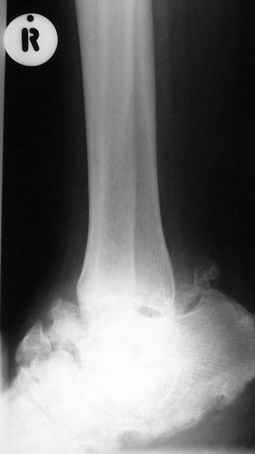

Кто шустрый - при какой патологии встречается так называемые "суставы Шарко"?Второе приобретение доктора Эмануэла мне понравилось своим романтическим названием: Candle bone - <кость-в-виде-оплывающей-свечи> : Просто редкая патология:

VR>Второе приобретение доктора Эмануэла мне понравилось своим романтическим названием: Candle bone - <кость-в-виде-оплывающей-свечи> : Просто редкая патология:

Мелореостоз

Остеосклероз при этом заболевании захватывает не всю кость по окружности, а простирается слегка волнистой

полосой вдоль длинной оси конечности (рис. 223, К), переходя через линию суставов на другие кости. Таким образом,

может оказаться пораженной целая верхняя или нижняя конечность или больший или меньший ее периферический участок,

по длиннику фаланги одного или нескольких, но никогда не всех пальцев. Описавшие эту болезнь в 1922 г. Жоани

(Joanny) и Лери (Leri) сравнивают остеосклеротические полосы с картиной, напоминающей стекающий со свечи и

застывающий стеарин или воск, отсюда и название "мелореостоз" - "стекающая вдоль конечности кость".

Измененный корковый слой, а также уплотненные эпифизы и мелкие губчатые кости приобретают плотность слоновой

кости. Корковый слой утолщается как в сторону костномозгового канала (эндостальная форма), в большей или меньшей

степени суживая его, так и наружу (периосталь-ная форма), возвышаясь над нормальным уровнем кости и увеличивая

этим ее наружный диаметр. Поверхность "наплывов" слегка волниста, с гребневидными возвышениями и углублениями, но

всегда резко конту-рируется. Склеротические полосы и ленты бывают чаще всего сплошными, но нередко они

прерывисты, расслоены. Иногда наблюдается некоторое удлинение костей и их небольшая дугообразная деформация, а